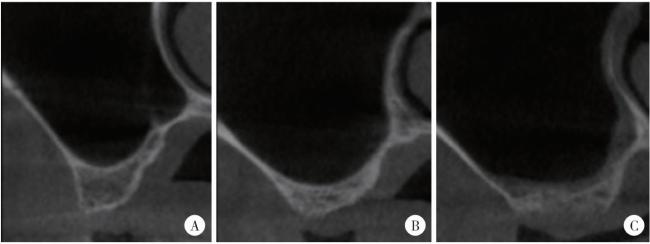

图3 上颌窦颊腭向轮廓

Figure 3 Morphology of maxillary sinus in the buccal and palatal directions

A, taper; B, round; C, flat.

纳入的种植体中包括宽型上颌窦31例(66.0%)、窄型上颌窦16例(34.0%);颊腭向轮廓方面,包括锥形17例(36.2%)、卵圆形20例(42.6%)、方形10例(21.3%)。

在常规上颌窦底提升术中,上颌窦颊腭向宽度与新骨形成百分比呈负相关,即窄型上颌窦更有利于成骨[27]。但关于宽度测量及分型方法尚无临床共识,多数医师倾向于以距离牙槽嵴顶10 mm为基准测量颊侧和腭侧骨壁之间的距离,也有研究认为应纳入多个高度位点以测量多个宽度值[28]。本研究采用前一种方法,并以Spinato等[16]提出的阈值将上颌窦分为宽型和窄型两类,结果显示宽型上颌窦和窄型上颌窦的成骨量差异无统计学意义,但锥形上颌窦形态较卵圆形有更多的成骨。